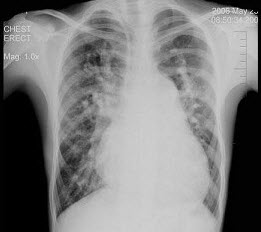

270、单项选择题

男,6岁。经常咳嗽、憋喘,呼吸急促、口唇青紫,进行性加重。X线检查如图,最可能的诊断为()

A.先天性PDA

B.先天性VSD

C.先天性ASD

D.法洛氏四联症

E.先天性肺动静脉瘘

271、单项选择题 “恶性骨肿瘤”最常见的骨膜反应类型是()